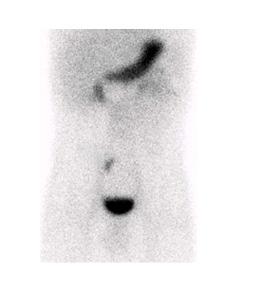

La scintigraphie au Pertechnétate de Tc99m est le test de choix pour identifier la muqueuse gastrique ectopique chez les patients dont la suspicion clinique est élevée. Cependant, quoique le diverticule puisse potentiellement être identifié sur la TDM faible dose si effectuée, s’il n’y pas de muqueuse gastrique ectopique ou cause de faux positif, l’étude scintigraphique par elle-même sera négative. Dans la scintigraphie au 99mTc-Pertechnétate, la captation du traceur est principalement au niveau des cellules sécrétrices de mucine mais son élimination est influencée par les cellules pariétales11,12. Sans manipulation pharmacologique, il y a élution du traceur de l’estomac vers le duodénum et le grêle en cours d’étude. Il est également visualisé l’élimination physiologique par les reins vers la vessie (figure 1 ).

Figure 1 : Examen effectué sans préparation pharmacologique et avec SPECT simple chez un patient de 4 ans avec rectorragies. Mise en évidence d’une élution du traceur en cours d’étude avec visualisation du duodénum et du grêle. Acquisition dynamique ( A ), cliché statique à 30 minutes post injection (B) et rendu 3D de l’acquisition tomographique (C)